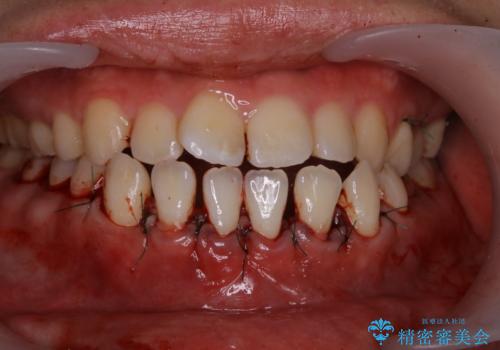

下の前歯は根の形がわかるくらい歯茎と骨がうすく、このままでは歯肉退縮のリスクがあります。

そのため、矯正治療の前に歯茎の移植と骨の再生治療を行うことにしました。